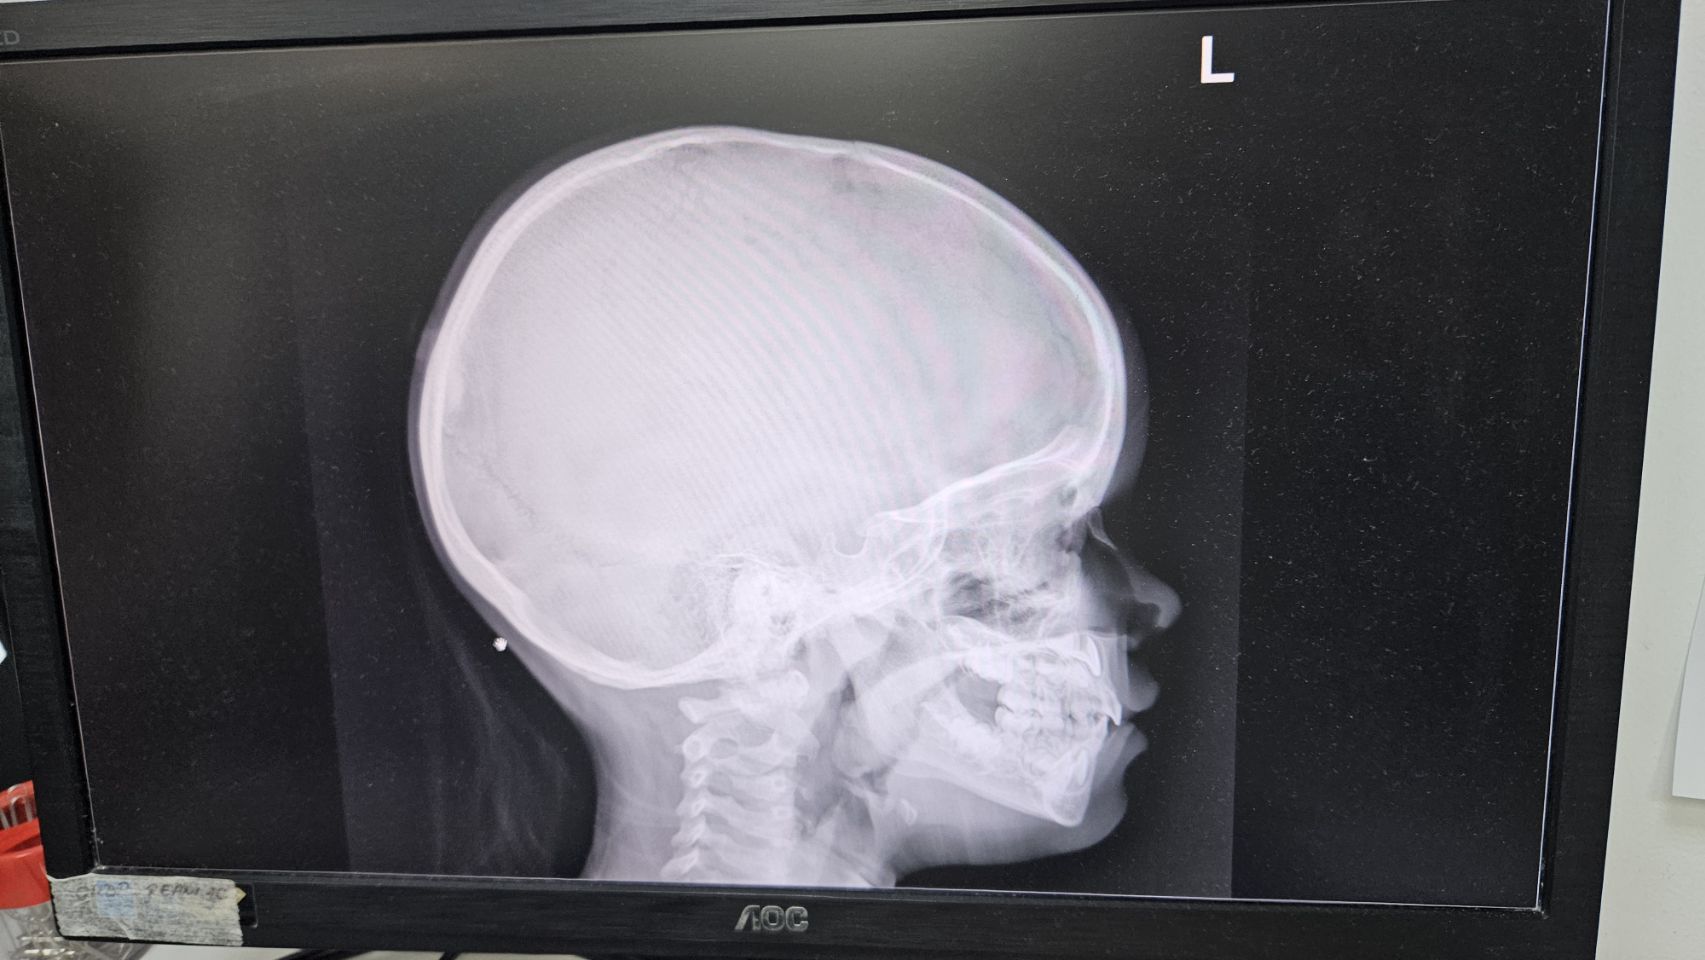

We are helped quickly in the hospital. In the meantime, Johan has applied for an emergency blue card online. This is immediately usable so that is also arranged. When we take a seat on the treatment table, the nurse takes a shaver and wants to start without saying anything. Hold on! We won’t do this like that. He looks surprised. The question of whether they want to share everything with Mirre so that she can discuss it with Jinte is well received. The question of whether all this can also be done without shaving, a little less. Fortunately it turns out not to be necessary! They want to clean it and numb it and then stich it up. Great, only Jinte does not want a puncture. That everything is in English is an advantage in this case. Mirre can translate everything child -friendly. Ideal! Jinte her favorite book is in her bag (top fellow that Johan) and helps enormously to distract. Jinte bravely gets through it. Also an X -ray and when it turns out to be good, we can go.